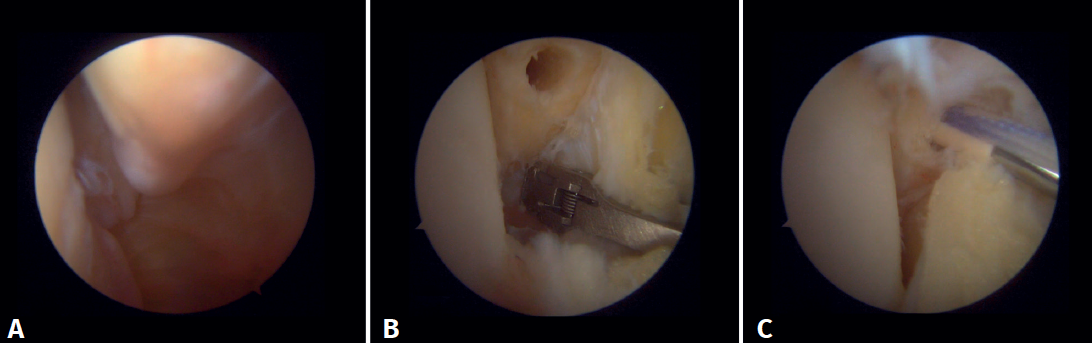

Surgical technique: arthroscopic treatment of acute medial complex injuries

In terms of surgical technique, the working portals are established in the same way as in conventional ankle arthroscopy: one anteromedial portal and one anterolateral portal. We always start with diagnostic arthroscopy to confirm the injury to the deltoid ligament. A probe can be used to verify the laxity of the fibers, and a test can be performed by inserting the probe through the medial groove: the lesion is confirmed if the instrument passes through. For repair, the viewing portal will be the anterolateral portal, thus allowing us to work more directly through the anteromedial portal. The anterior fibers of the superficial tibiotalar and intermediate fibers of the deep portion of the deltoid ligament are the ones that can be repaired with the arthroscopic technique(38). Once the ligament has been identified and dissected, a suture is passed between the fibers using a suture passer. The medial malleolus anchorage zone is prepared with a shaver or a small burr. With the ankle in neutral position, the anchor is inserted while maintaining the tension of the sutures. The intersection of the line parallel to the tibiotalar joint and a perpendicular line marked from the tip of the malleolus and along the lateral border of the malleolus can be used as an anatomical reference for placement(21). After reduction, we again test the fibers for tension and passage of the probe through the medial groove, to confirm adequate repair (Figure 8).

Información del artículo